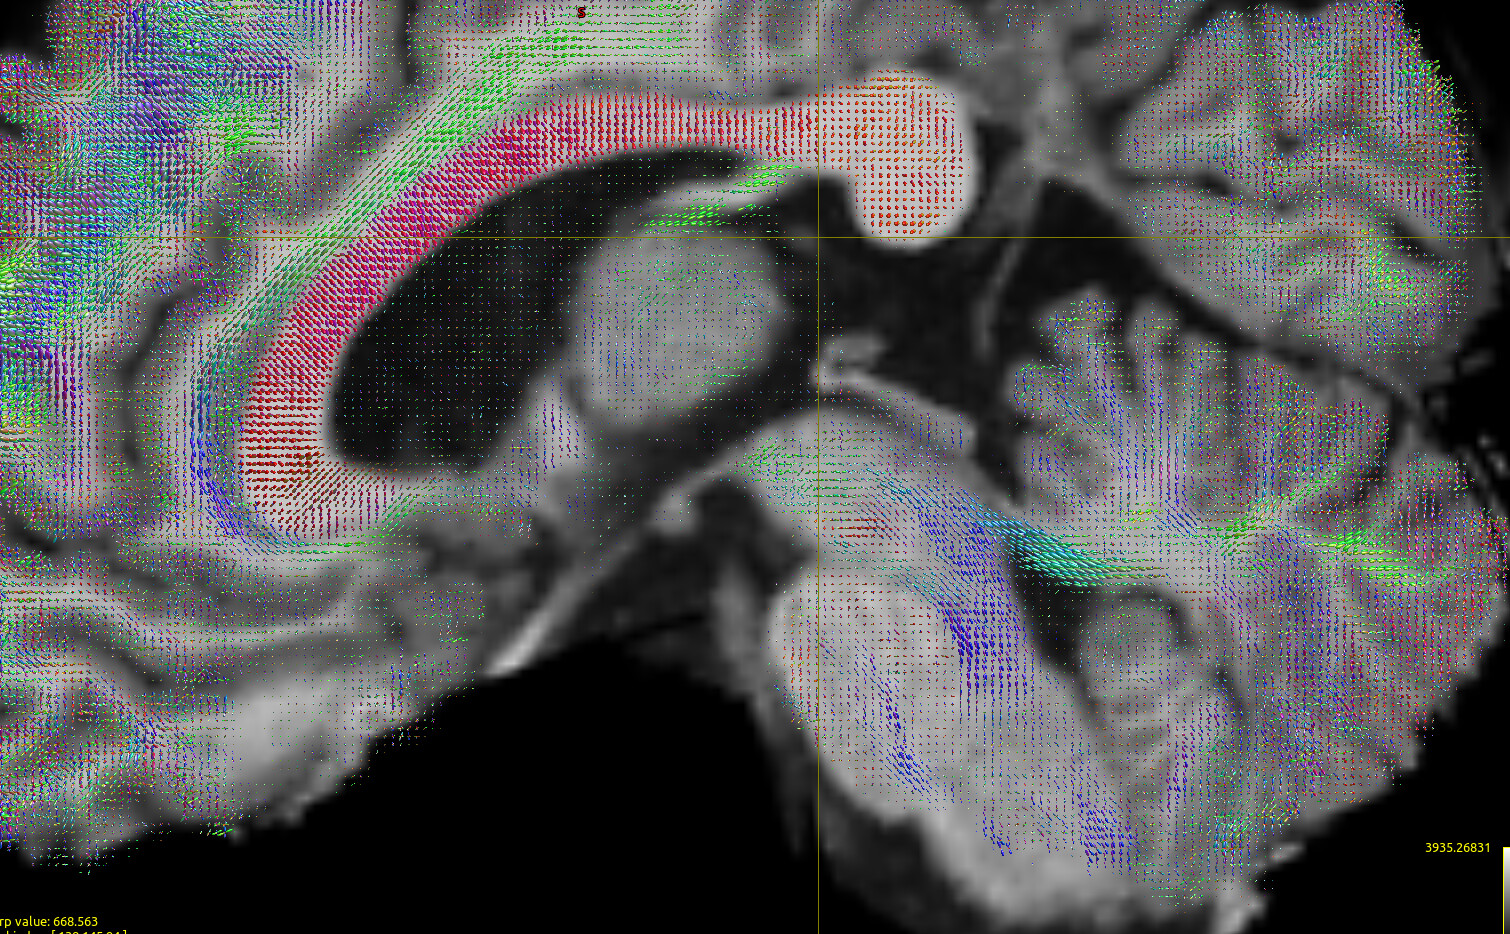

FODs:

In order to do some sanity check I have turned to HCP data; I have selected the b1000 shell, computed the response function using the Tournier method,

which leads to seemingly OK FOD data:

Using iFOD2 here as well, this time with

and seeding the entire WM. Note that I changed the min length here to try to see if that is a problem for the high res data/see if I get better results for HCP. Changing the cutoff down to 0.04 improves results only a tiny bit, but overall I still get poor results for the cerebellar region (below). The first thing that strikes me is that the MCP is unable to properly contour the pons: